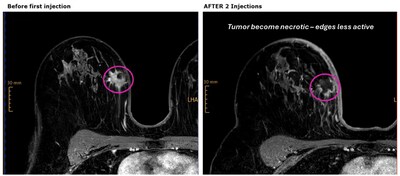

SHELTON, Conn., June 11, 2025 /PRNewswire/ — Intensity Therapeutics, Inc. (Nasdaq: INTS) (“Intensity” or the “Company”), a late-stage clinical biotechnology company focused on the discovery and development of proprietary, novel immune-based intratumoral cancer therapies designed to kill tumors and increase immune system recognition of cancers, announces first few patients receiving INT230-6 achieved high levels of necrosis after 8 days in the Phase 2, INVINCIBLE-4 study, before they initiated the standard-of-care regimen as shown in Figure 1.

“We are encouraged to see high levels of tumor necrosis from the MRI scans and evidence of tumor inflammation after two INT230-6 injections and before initiation of the SOC in our first patients,” said Ursina Zürrer, M.D. Chief Physician for Genetic Counseling, Department of Medical Oncology and Hematology Cantonal Hospital Winterthur, Switzerland, and the Coordinating Investigator for the INVINCIBLE-4 Study. “We are encouraged that these patients achieved such a good response to INT230-6 prior to their beginning the Standard immune-chemo regimen and look forward to continuing enrollment in the study.”

“We are excited to see that INT230-6 is achieving meaningful levels of necrosis in patients with evidence of immune activation. TNBC Patients who have no live cancer in their tumor or nodes at the time of surgery have a significantly improved event-free survival advantage compared to those who do not have a pathological complete response. TNBC patients risk their lives to achieve a pCR, and about forty percent fail to achieve the desired result. We look forward to seeing the pathological complete response data being generated by our partners at SAKK and Unicancer,” said Lewis H. Bender, President and CEO of Intensity.